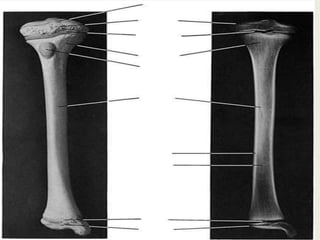

A typical long bone consists of :

- Epiphysis

distal to the physis

(growth plate )

-Metaphysis

on the opposite side

of the physis from the epiphysis

-Diaphysis

is the long shaft beyond

the metaphysis

Introduction longbones A typical longbone consists of : - Epiphysis distal to the physis (growth plate ) -Metaphysis on the opposite side of the physis from the epiphysis -Diaphysis is the long shaft beyond the metaphysis